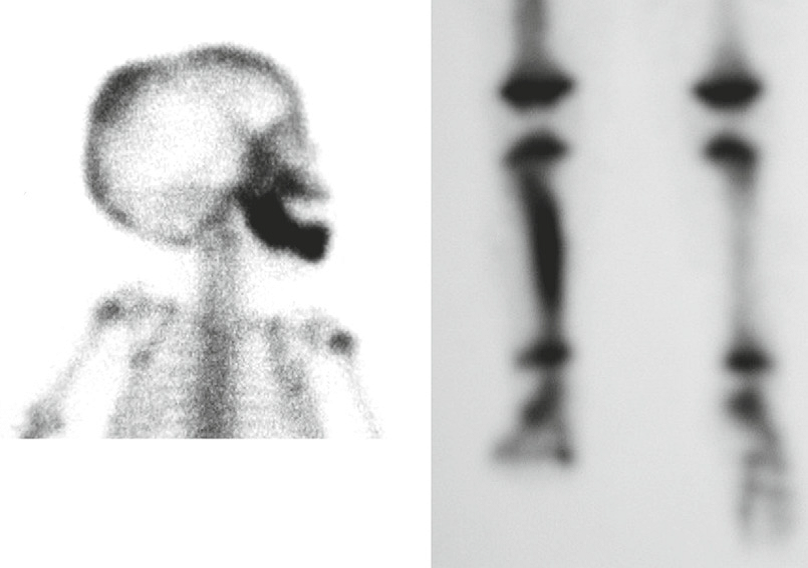

Legg-Calve-Perthes disease A, Radiograph of the left hip, with frog-leg positioning, shows crescentic subchondral lucency (arrow), consistent with necrosis. The femoral epiphysis is irregular and sclerotic and shows loss of height compared to the normal left femoral head. B, T1-weighted coronal MR image shows loss of the normal fatty signal in the right femoral epiphysis (arrow). There is also mild loss of height.

Legg-Calve-Perthes disease Bone scintigraphy with pinhole collimation of both hips shows absent uptake (arrows) in the left femoral epi- physis, consistent with an avascular necrosis. Note normal uptake on right.

## Footnote Legg-Calve-Perthes disease Chronic changes in a node-fragmented, shortened capital femoral epiphysis with metaphyseal ‘‘cyst’’ (arrowhead). Note widening of femoral head and neck (coxa magna; arrows). There has been left surgical acetabular reconstruction to create acetabular coverage of the enlarged left femoral head.